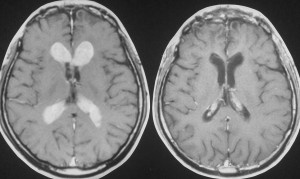

脳室上衣下浸潤(剖検例)

subependymal infiltration (autopsy)

1992年の剖検所見

大脳表面,脳幹部,脊髄くも膜下腔には腫瘍が見当たりませんが,側脳室を充満するように腫瘍が増殖しています。

側脳室壁に結節状の腫瘍が無数に認められます。これは今日では,内視鏡による脳室内観察で見ることができるものです。